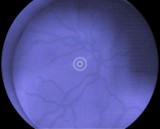

RetinaScope es la cámara de imágenes de retina no midriática (*) portátil WFC-01 nun+, de bajo costo y fácil de uso. Es una herramienta para inspección de la retina y para la detección precoz de enfermedades oculares como la retinopatía diabética, la degeneración macular (relacionada con la edad DMAE*) y el glaucoma.

SOFTWARE RSPlus

RSPlus es el software de RetinaScope que se suministra junto con el Retinógrafo portátil WFC-01 NUN+ (Con certificación MDR clase 1, nun+ de WikiOptics) y un smartphone Android de gama alta (Xiaomi POCO). El pack tiene la intención de realizar imágenes de la retina del ojo humano para su posterior diagnóstico de la degeneración macular, retinopatía diabética y el glaucoma.

Visión Normal

Degeneración Macular Asociada a la Edad